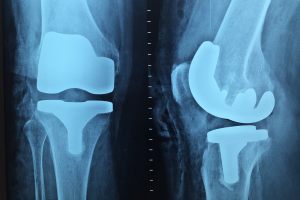

Ortopedie

Ambulator Clinic Europa vă oferă servicii medicale adecvate pentru cele mai multe afecțiuni ale aparatului locomotor. Din orice cauze ar proveni acestea, respectiv traumatisme, inflamații sau boli degenerative, congenitale sau oncologice.

Vă oferim soluții și metode moderne de tratament pentru recuperare medicală, indiferent de natura și dimensiunea traumatismului.